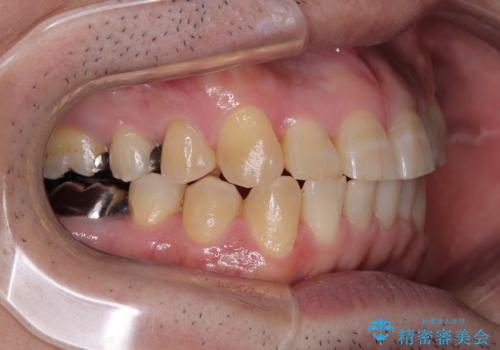

- 近医にてブリッジ治療を行った歯が痛くてたまらないとのことで来院された患者様です。

診察を行ったところ、奥の土台になっている歯は神経組織が失活しており、根尖部に病変があり、そこが原因で痛みを生じている状態でした。

根管治療を行うためにブリッジを除去したところ、むし歯が歯肉の奥深くにあまで及んでいたため、歯周外科処置によりむし歯が歯肉縁より浅い位置へと改善することとしました。